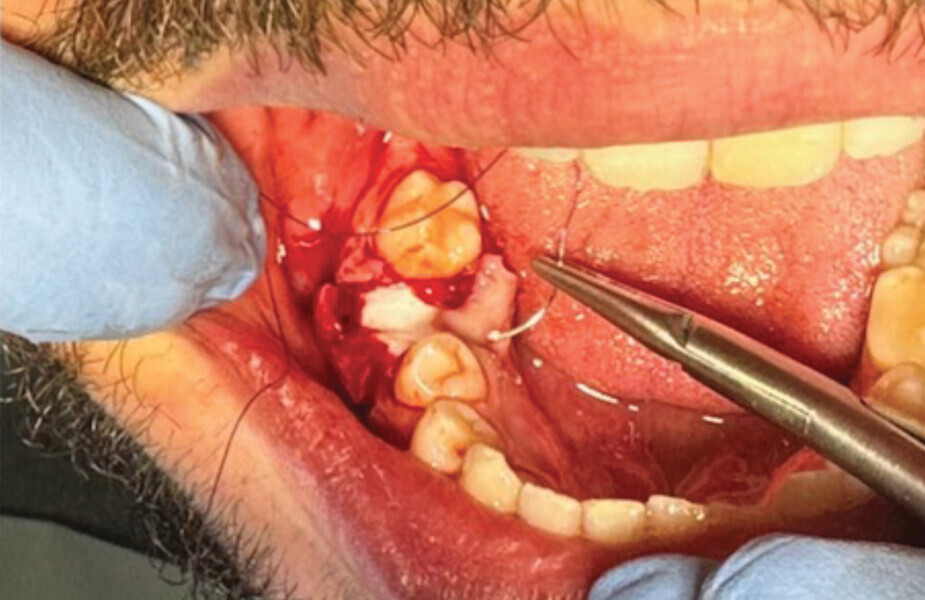

Fig. 9

Lors de la réouverture pour la pose de l’implant, nous avons pu constater que la hauteur de l’alvéole a été préservée, et la constitution de néo os alvéolaire de belle consistance nous a permis la pose de l’implant en toute sécurité (Figs. 9 et 10).

Étapes de l’intervention implantaire